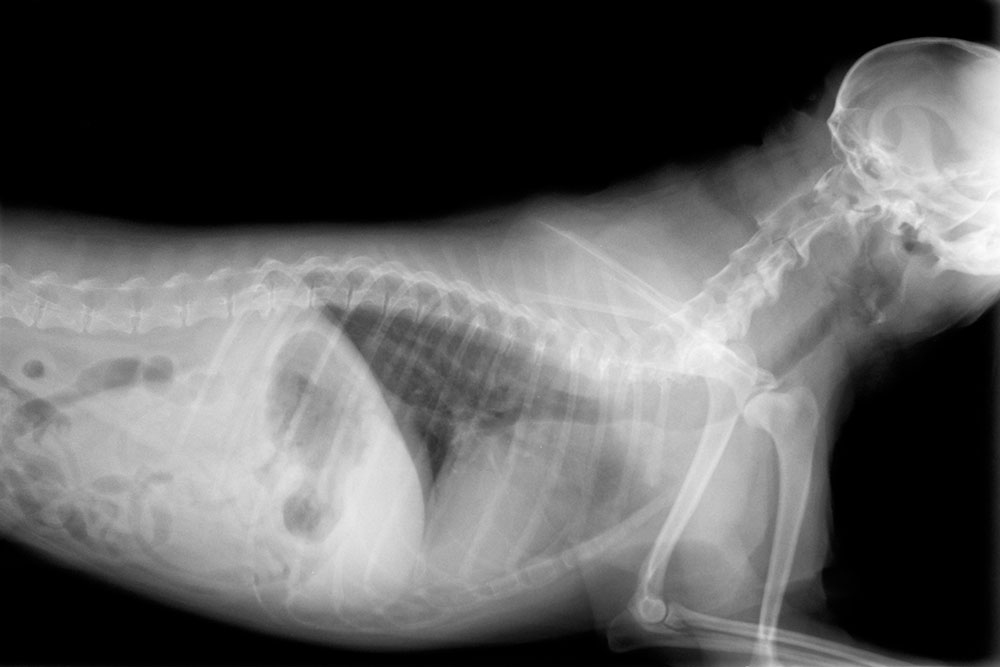

We use in-house diagnostics like ultrasound, X-rays, and lab work to identify heart changes quickly, so we can start treatment before the disease progresses. Our digital radiography provides clearer images of heart size and shape, while ultrasound allows us to evaluate heart structure, blood flow, and valve function in real time. If your pet hasn’t had a checkup in a while or you’re noticing any changes, request an appointment to begin a cardiac evaluation.

Our digital radiography reveals heart size and shape changes, as well as fluid accumulation in the lungs. Physical examinations help us detect heart murmurs and other abnormalities through careful listening. Combined with bloodwork from our in-house laboratory, these tools provide comprehensive cardiac assessments and help us monitor how well treatment is working over time.